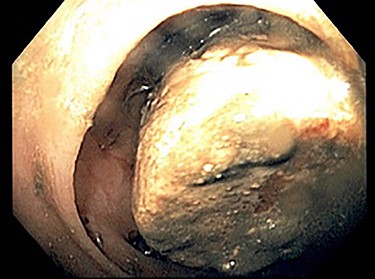

She was admitted and fluid rehydration was provided. Her symptoms improved and her abdominal exam remained benign. Daily abdominal radiographs were obtained to monitor transit of the gallstone; however, by hospital Day 3, she was unable to pass the stone and radiograph imaging failed to reveal movement beyond the location seen on admission CT. She was consequently taken to the endoscopy suite for flexible sigmoidoscopy. The large mobile gallstone was encountered at 40 cm (Fig. 2) and was grasped with a snare but was unable to be extracted beyond the rectosigmoid junction, which appeared narrowed. The procedure was then aborted.